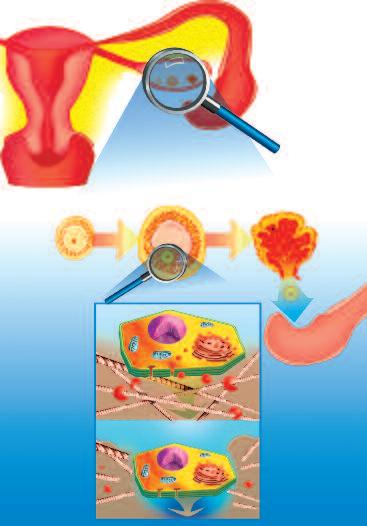

Il processo di ovulazione nel corpo femminile è una delle funzioni più affascinanti in cui il corpo utilizza un meccanismo di dissoluzione del collagene. I cambiamenti ormonali mensili del ciclo femminile stimolano certi tipi di cellule (granulociti) che circondano la cellula uovo in fase di maturazione all'interno dell'ovaio (follicolo).

In condizioni di normali, stimolati dagli ormoni (ad esempio gli estrogeni), i granulociti iniziano a produrre liquidi ricchi di questi enzimi che dissolvono il collagene. Questo avviene a metà del ciclo mestruale femminile, la cellula uovo matura è circondata da questi enzimi che dissolvono il collagene, per cui il collagene della parete ovarica si assottiglia fino a formare un buco. Questa apertura è abbastanza grande solo per permettere alla cellula uovo di passare dalle ovaie attraverso il piccolo canale di collegamento (trombe di Falloppio o tube ovariche) nell’utero.

E' chiaro che questo meccanismo deve essere perfettamente sincronizzato e limitato a questa specifica ubicazione. Questo meccanismo deve far sì che una sola cellula uovo per ogni ciclo mestruale passi e inizi il suo viaggio verso l'utero. Pertanto, è assolutamente importante che gli enzimi di dissoluzione del collagene entrino in azione quando sia necessario e solo in una specifica ubicazione, dove poi il meccanismo che blocca questi enzimi avvia l’auto-guarigione del tessuto.

Subito dopo che la cellula uovo ha lasciato l’ovaio, l'attività degli enzimi che dissolvono il collagene è fermata da altri blocchi enzimatici del corpo, che riequilibrano i meccanismi di produzione di collagene, poiché hanno la meglio sul processo di dissoluzione dello stesso. Utilizzando questo meccanismo, il tessuto della parete dell'ovaio può guarire e chiudersi rapidamente. Quattro settimane dopo, l'intero processo si ripete.

Questo accade nella parete dell’ovaio

L’ovulo inizia la sua migrazione verso l’utero

La produzione di enzimi che digeriscono il collagene, stimolata dagli ormoni, fende il tessuto dell’ovaio per alcuni secondi – il tempo necessario affinché la cellula uovo matura lasci l’ovaio e possa migrare nell’utero.

L’immagine A mostra il momento in cui la cellula uovo matura lascia l'ovaia, attraverso un piccolo foro biologicamente creato nelle pareti di questo organo Gli enzimi che digeriscono il collagene (pacmen rossi) vengono aggiunti per illustrare questo processo biologico

L’immagine B mostra una cellula uovo (al centro) vista ad un microscopio molto potente. I piccoli dossi che circondano questa grande cellula sono le cellule (granulociti) specializzate nella produzione di grandi quantità di enzimi che digeriscono il collagene necessario per l'ovulazione.

perché alcune forme di cancro sono più frequenti di rispetto ad altre?

La nostra ricerca ha fornito una risposta anche a questa domanda chiave. Il cancro si sviluppa spesso particolarmente negli organi che utilizzano già la digestione del collagene in normali condizioni fisiologiche. Il primo gruppo di organi colpiti sono gli organi riproduttivi. In particolare, gli organi riproduttivi femminili subiscono alterazioni funzionali (ormonali) e strutturali, profonde e ripetute.

In questo capitolo abbiamo già parlato dei profondi cambiamenti del corpo femminile durante l'ovulazione e l'allattamento. In modo analogo l’utero e il collo dell’utero (cervice) sono sottoposte ad una ristrutturazione tessutale, in relazione al ciclo mensile e alla gravidanza, che richiedono un’intensa attività di enzimi che digeriscono il collagene. Non sorprende che questi organi siano i più sensibili ad una demolizione incontrollata del proprio tessuto connettivo e siano, quindi, più esposti al cancro.

Per le stesse ragioni, pure gli organi riproduttivi degli uomini, prostata e testicoli, sono colpiti dal cancro con maggiore frequenza rispetto ad altro organi.

Un altro fattore correlato a questa maggiore incidenza del cancro negli organi riproduttivi femminili e maschili è la loro attività ormonale che stimola la produzione delle collagenasi in questi organi. Livelli ormonali superiori alla norma - prodotti autonomamente dal corpo o causata da somministrazione di farmaci ormonali (contraccezione, terapia ormonale sostitutiva) aumentano il rischio di tumori in questi organi.